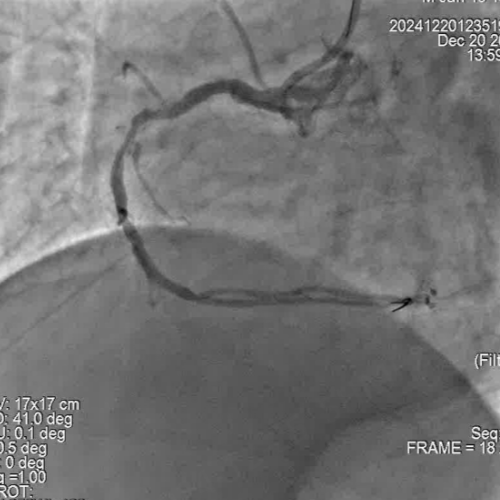

冠脉造影

手术过程

尹秋林主任表示本次手术很顺利。该患者左冠和右冠病变均较为局限,且患者及家属对植入生物可吸收支架意向强烈。在腔内影像IVUS的引导下评估管腔尺寸,病变性质后做精准预处理。本次手术中FIRESORB®具有较好的推送性,径向支撑表现也很好。我们会持续关注患者术后的恢复情况。